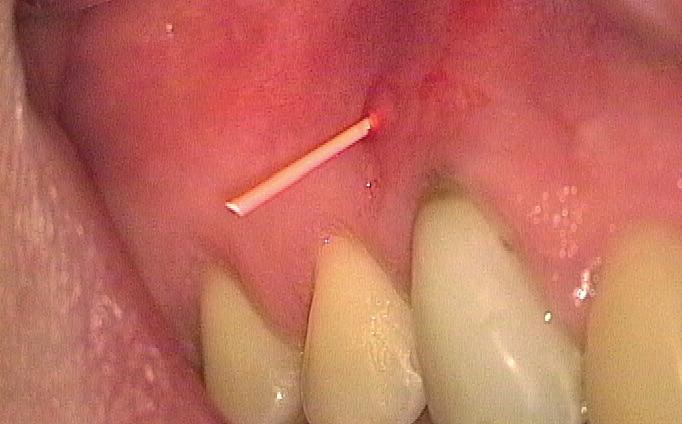

Stap 2: Preparatie van element en gingiva

Verwijder carieus tandweefsel en maak bij twijfel gebruik van een cariësdetector. In veel gevallen zal het voorkomen dat je subgingivaal eindigt. Gingiva dat in de preparatie ligt kun je verwijderen met bijvoorbeeld een elektrotoom. Ikzelf maak gebruik van

een draadloze warmtespreader, de Superendo Alpha (afbeelding 3 en 4).